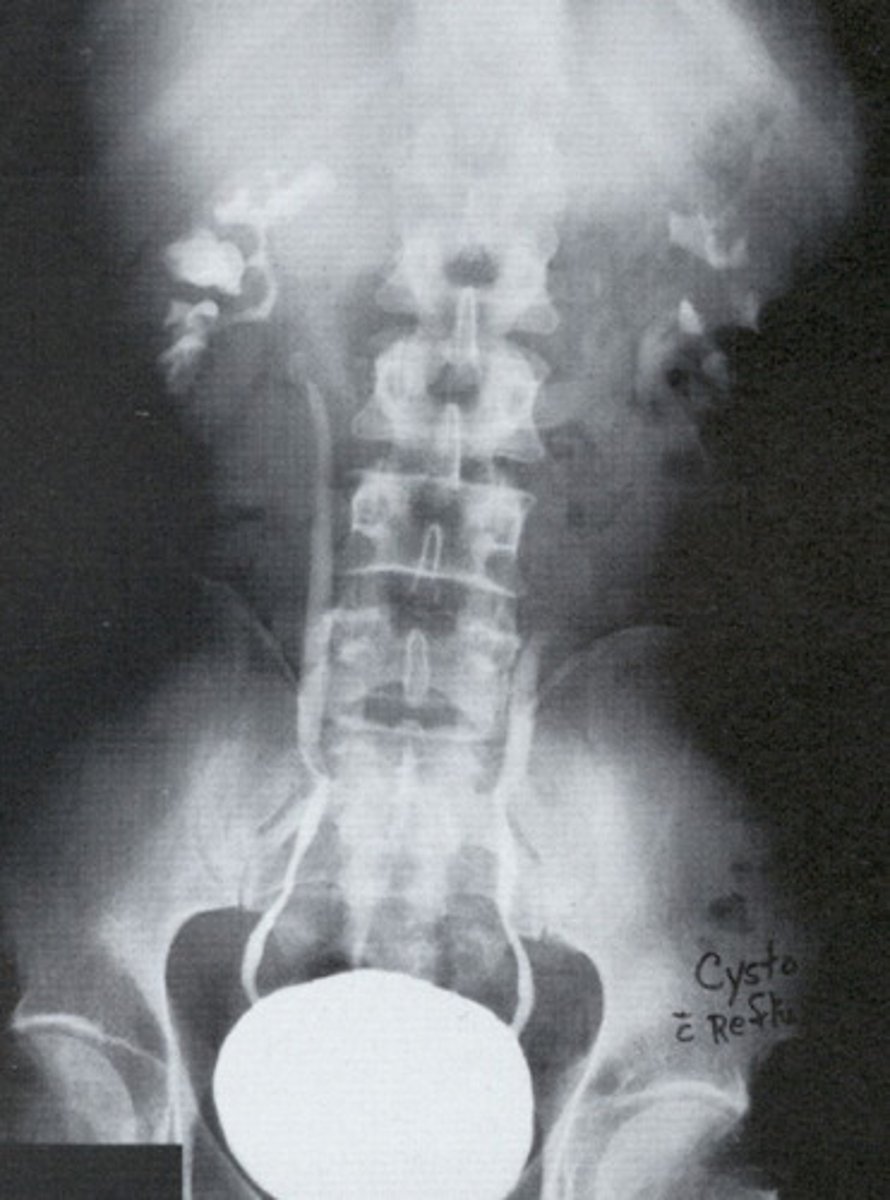

Reflux

What is this pathology?

- Uteroceles

- "Cobra Head"

- With surgery

- What congenital anomaly refers to the cyst-like dilation of the distal ureter where it enters the trigone of the bladder?

- How does this pathology appear radiographically when the bladder is contrast-filled?

- How is this pathology treated?